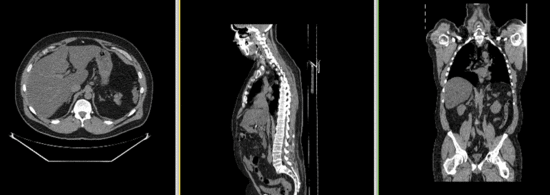

this is the fixed CT image. All images are aligned into this space this is the fixed PET image. All images are aligned into this space lleft this is the moving image. The transform is calculated by matching this to the reference image this is the moving image. The transform is calculated by matching this to the reference image

fixed image/target fixed image/target moving image moving image

• reference/fixed : baseline CT: 0.97 x 0.97 x 3.27 mm , 512 x 512 x 267; PET: 4.7 x 4.7 x 3.3 mm , 128 x 128 x 267

• moving: CT: 0.98 x 0.98 x 5, 512 x 512 x 195; PET: 4.1 x 4.1 x 5 mm, 168 x 168 x 195